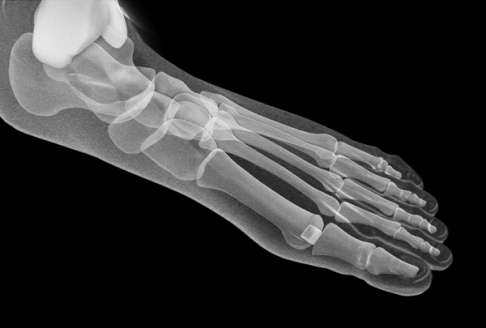

Inzwischen arbeiten wir mit einer haltbaren und stabilen Alternative für die Prothesenversorgung des Großzehengrundgelenks: der sogenannten Hemiprothese oder Oberflächenersatzprothese. Bei einem Oberflächenersatz wird nur ein Gelenkpartner im Großzehengrundgelenk - der Metatarsalknochen - durch den elastischen Oberflächenersatz bedeckt. Die natürliche Gelenkpfanne des Großzehengrundgelenks bleibt unverändert erhalten. Damit ist die Hemiprothese ein sehr knochensparendes operatives Verfahren.

Die Hemiprothese unterscheidet sich deutlich vom vollständigen Gelenkersatz des Großzehengrundgelenks (Totalendoprothese). Nur eine der beiden Gelenkflächen wird mit einer Prothese versorgt. An der gegenüberliegenden Gelenkfläche mit der Gelenkpfanne am Zehenknochen wird kein Implantat gesetzt. Die Oberflächenersatzprothese verbindet sich direkt gelenkig mit der natürlich vorhandenen knöchernen Gelenkpfanne. Im Gegensatz zur Versteifung des Gelenks kann die Bewegungsfreiheit im Gelenk komplett erhalten oder wiederhergestellt werden.

Die Besonderheit einer Hemiprothese besteht darin, dass am basalen Gelenkteil - dem Mittelfußknochen - lediglich eine Cheilektomie durchgeführt und keine Prothese eingebracht wird. Im Gegensatz dazu sind alternative Eingriffe wie etwa eine TEP oder auch die Versteifung immer mit einer Resektion des Mittelfußköpfchens verbunden und daher nicht knochensparend durchführbar.